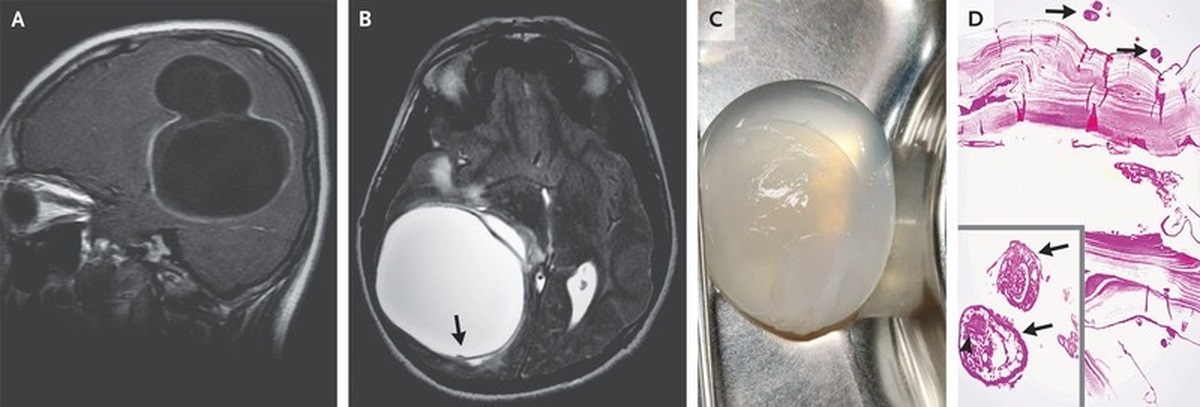

Эхинококк Печени Фото

Эхинококк Печени Фото 112 фотографий